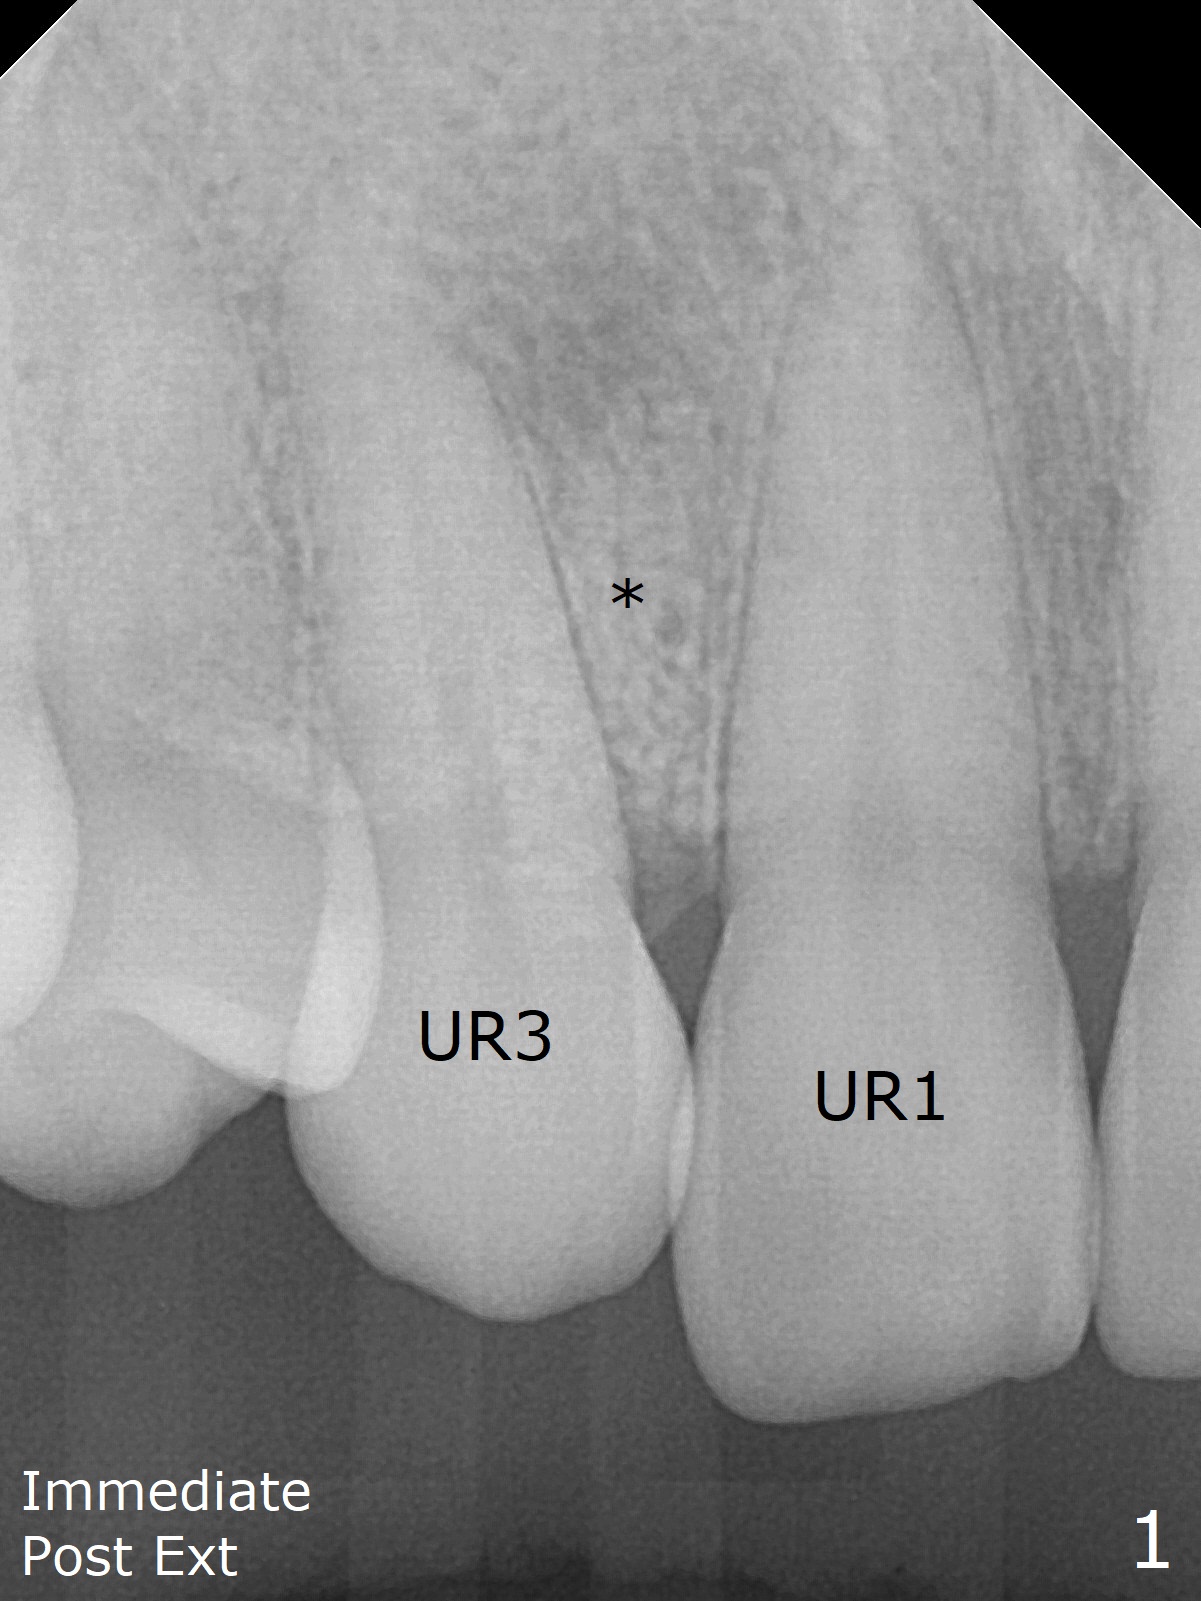

The 54-year-old woman returns for ortho-dontic treatment 1.5 months post extra-ction of UR2 (Fig.1,2). Brackets, bands and 14 niti wire are placed in the upper arch, whereas insufficient spaces are created for placement of the lower arch molar bands. Since there is no horizontal space issue, the cross bite canine is able to be corrected immediately when the vertical clearance is obtained (Fig.3,4). In fact composite is added to the 1st molars in a few days, since that in one of the 2nd molars dislodges. UR3 cross bite is nearly corrected < 2 months post banding (Fig.5), while brackets are placed in the lower arch (Fig.6 (coronavirus)). It appears that the lower arch will be too large when it is expanded for the upper one.